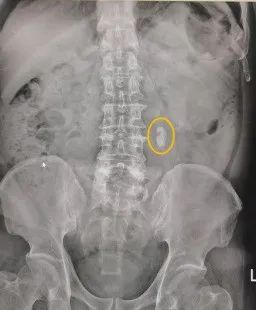

提起泌尿系结石,很多人的第一反应是不痛就不需要治疗。但是你知道吗?有一种结石,不痛但却更危险。 顺德一名患者在3年前因其他疾病就诊,完善各项检查时发现有输尿管结石,但因“没什么感觉”便没有重视,直至近日才发现病情加重,左肾严重积水,几乎毁掉一个肾,令人遗憾。 ky泌尿外科主任罗力教授提醒:结石不痛不代表没有危险,输尿管结石长时间不治疗,可严重损害肾功能。 近日,顺德市民李先生到家附近的社区卫生服务中心做体检时,发现其左肾已遭受“重创”。B超检查后,医生告诉他,他左肾严重积液,像个皮囊,建议他尽早到大医院治疗。 次日,李先生便来到了ky泌尿外科就诊。经检查,李先生左输尿管上段结石,大小约2*1.5cm;并上输尿管及左肾重度积水、肾实质萎缩,肾功能估计所剩不多,左肾内还有多发小结石。 术前CT片:可见输尿管结石以及严重肾积水 据李先生自述,其实他早在3年前就发现输尿管有结石,当时因为脑梗就诊,在做B超时医生就发现了,但因一直感觉不痛,也没有其他症状,因此没有进行治疗。“这结石又不痛,也没任何感觉,没想到会这么严重,不然早就来治疗了”,李先生悔不当初。 对此,ky泌尿外科主任罗力教授表示,输尿管结石通常在移动时会引起绞痛,但结石固定不动时疼痛不明显甚至不痛,加上个体对疼痛的耐受力不同,会存在不痛的情况。“但是,不痛不代表没有危险,结石长期嵌顿会导致输尿管梗阻,使尿液无法正常排出,从而引起肾积水、损害肾功能,积水逐渐加重,长时间不治疗则可能毁掉整个肾”。 虽然李先生左肾重度积水,肾皮质很薄,但是考虑到还有小部分肾功能,以及长期梗阻可能引起感染,因此罗力教授还是建议他积极治疗,挽救部分肾功能。 诊断明确后,罗力教授为其施行了左侧经皮肾镜钬激光碎石取石术,一次性清除了输尿管上段的结石及左肾多个小结石。解除结石梗阻后,患者肾积液也就逐渐缓解。 罗教授表示,由于耽误治疗时间过长,肾积水情况严重,李先生的左肾估计有近八成的功能已经丧失。 左图:术前平片可见输尿管结石 右图:术后平片可见结石影消失 输尿管结石多数来源于肾脏,即由肾脏移动至输尿管,进而导致一系列梗阻症状,如腰腹部疼痛、恶心呕吐、尿急、尿频、尿痛、血尿等,当继发感染时疼痛会加重,甚至有发热、乏力、体虚等表现,但也有部分患者可以长期无症状。 “临床上,像李先生这样无症状的患者并不少见,这种‘沉默的结石’更需警惕!”罗力教授提醒:不痛的输尿管结石容易被忽视,甚至比引起疼痛的结石造成的伤害更大。随着结石的逐渐增大,以及刺激输尿管壁引起炎性息肉反应,最终被息肉紧紧包裹,肾积水逐步加重,等发现时往往伴有较为严重的肾积水,肾脏功能也会有相应的损伤,严重的患者甚至出现患肾功能丧失、继发肾性高血压,或因感染发展为肾积脓。 既然是“沉默的结石”,那么患者怎样才能对结石做到早发现呢?罗力教授介绍,目前泌尿系结石筛查首选B超检查,简便、经济、无创伤,为常规体检项目,市民只需定期体检就能实现结石的早期筛查。 另外,即使查出输尿管结石也无需紧张,通常直径小于5mm的输尿管结石,有部分会自行排出,可以采取保守治疗;而直径大于6mm的输尿管结石则可能需要体外碎石或外科干预。 “对此,市民也无需担忧,得益于微创技术的不断进步,输尿管结石的手术已经可以实现无创化治疗了。”罗力教授介绍,一般不开刀即可完成碎石取石,术后也仅需恢复1-2天即可出院。